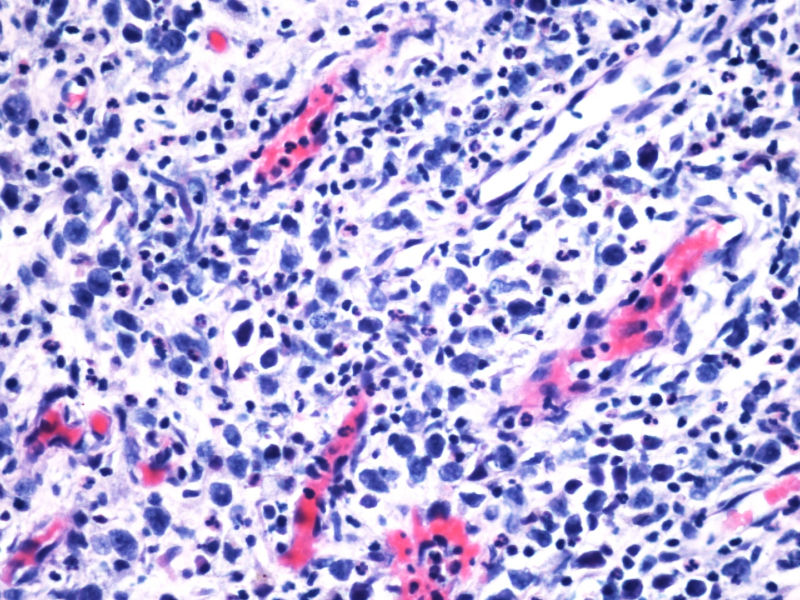

最终诊断为:ALK阳性的间变性大细胞淋巴瘤,淋巴组织细胞变异型。

拿出来的目的:本例始发于骨骼,临床提示脓肿或骨髓瘤,ALK阳性但EMA阴性,细胞毒只有一个标记阳性,本例CD4不阳性。因为CD30和CD15均有非肿瘤细胞阳性的情况,所以对于这个骨骼病例,细胞少而退变,因此最初没有信心诊断,但ALK一般不在非肿瘤细胞内阳性表达,所以最终还是诊断了ALCL。

2)肿瘤细胞免疫表型特殊, CD30+CD15+ALK-1+CD43+Perforin+, 而其他PanB细胞和PanT细胞的标记均为阴性。

3)楼主诊断ALCL主要根据是 ALK-1+, 很有说服力!